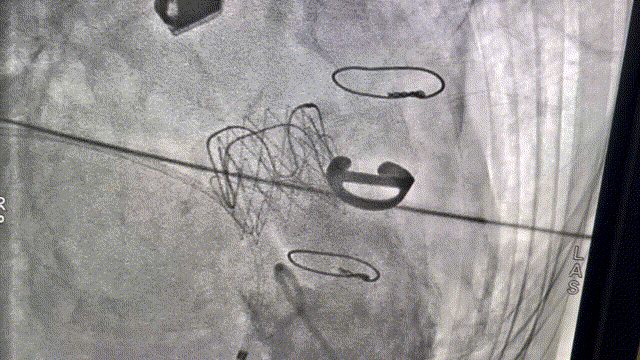

病例二植入后造影